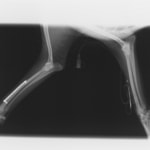

症例3:キルシュナーワイヤーのピンニングによる整復

ペルシャ猫 11ヶ月齢 雄

他院にて左大腿骨遠位の成長板骨折(salter-harrisⅠ型)が認められており、治療相談を目的として来院。当院にて、キルシュナーワイヤーを用いたピンニングにより骨折部位の整復を行いました。術後の経過は良好で、現在も経過観察中です。

術前レントゲン

術後レントゲン

Arthrex社のターゲティングデバイスを用いてピンニングの位置を調整することで、確実な固定を行っています。当院ではこの手術器具以外にも、人の手術にも使用される様々な器具を導入し、手術精度を高め、また医療メーカーと新しい器具の開発、試作にも取り組んでおります。